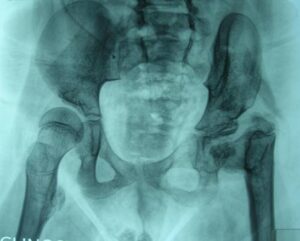

- Sublussazione e lussazione. Si tratta di una problematica molto frequente nei bambini con mielomeningocele: generalmente è lo squilibrio tra muscoli flessori/adduttori funzionanti ed estensori/abduttori ipovalidi che provoca la progressiva alterazione dei rapporti tra femore ed acetabolo fino alla lussazione completa.

Il trattamento richiede un’accurata valutazione funzionale (valutazione della funzione muscolare, del livello neurologico, dell’obliquità del bacino, dell’allineamento del rachide, della capacità deambulatoria, ecc) e non una semplice valutazione radiografica.

Il quesito fondamentale riguarda l’opportunità o meno di procedere a complessi interventi di riduzione delle lussazioni e ricostruzione articolare.

Infatti bisogna considerare da un lato i possibili vantaggi di una riduzione (in particolare, stabilizzare l’articolazione, evitare differenze di lunghezze tra i due arti, prevenire l’obliquità del bacino e la scoliosi) ma dall’altro l’elevato tasso di complicanze che possono essere associate al trattamento (rischio di rigidità, fratture, ossificazioni in sede di intervento, alto rischio di recidiva della lussazione dopo il trattamento).